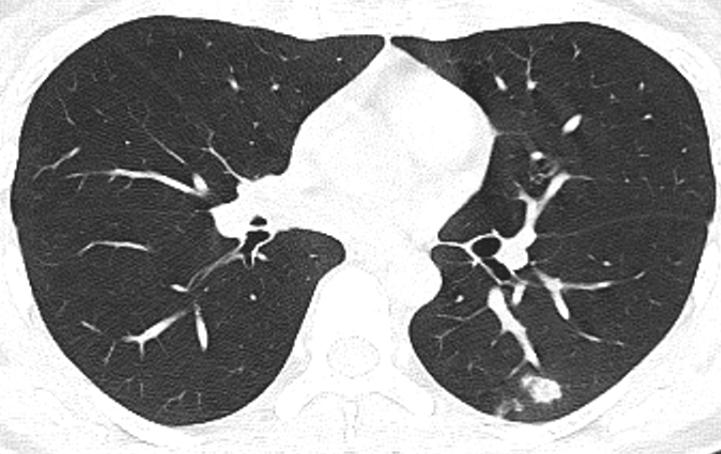

胸部CT示:双肺多发磨玻璃结节,左下叶背段散在实性结节,散在小空洞,部分支气管的管壁增厚,如下(图1~17)。